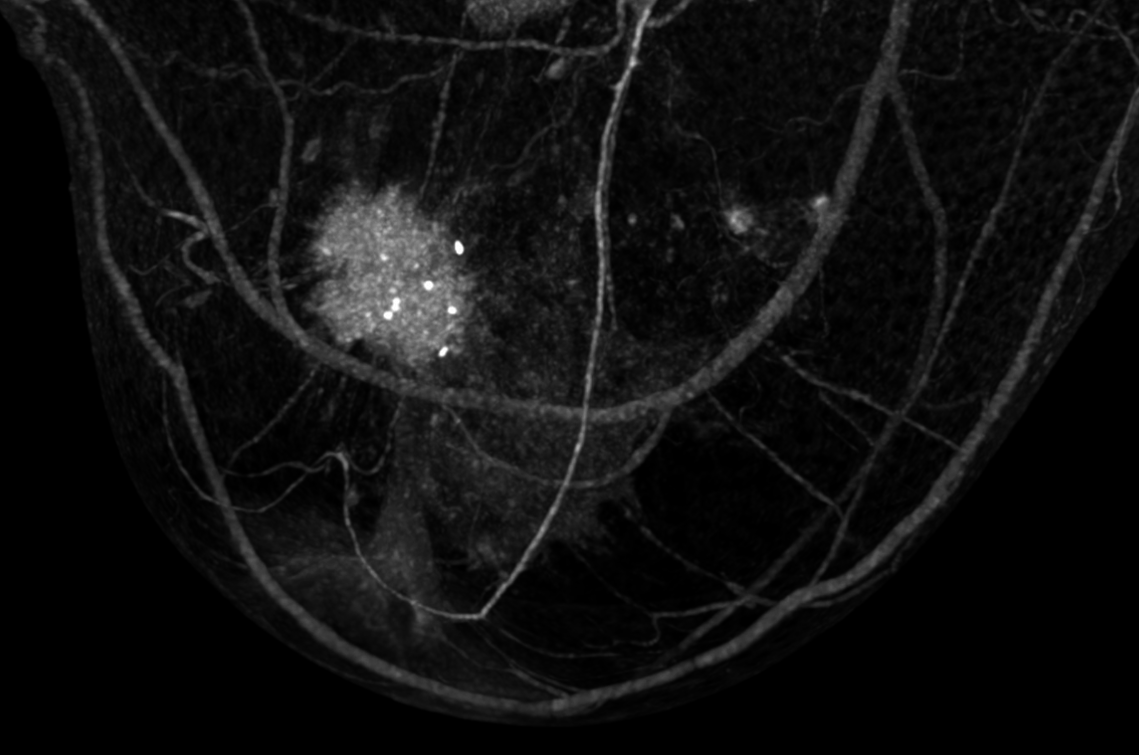

These tissue densities differed significantly between malignant lesions and dense breast tissue without findings (p < 0.001), between malignant lesions and cysts (p < 0.001) and between fibroadenomas and dense breast tissue (p ≤ 0.003; see fig. 1).

Differentiation between different lesions and dense breast tissue without clinical findings with significant differences in tissue density.